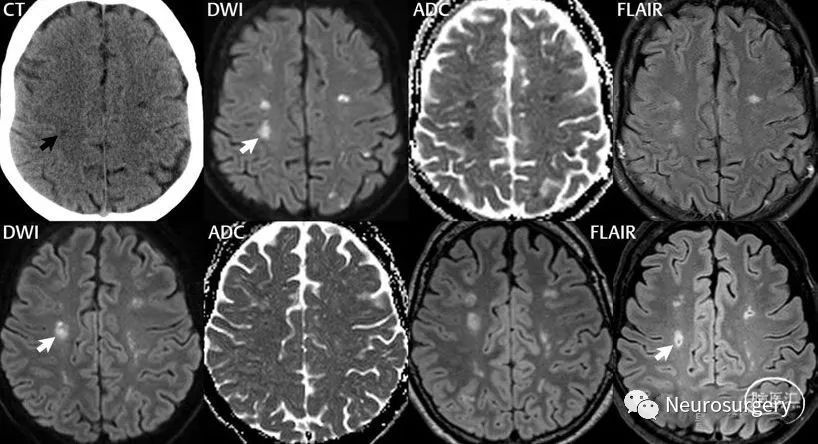

图2:白质局灶性小梗死(分水岭区,低灌注引起)演变。箭头表示4次检查同一病灶。上左一图为首次CT,上左二图为首次MR,下左一图为10天后MR,下右一图为3个月后MR。上排图像为发病时基线检査,DWI发现多发白质和皮层小梗死,CT仅能显示2个病灶(说明CT敏感性低)。病灶同时有细胞毒性水肿(DWI高信号,ADC低信号)和血管源性水肿(FLAIR高信号;但是右侧大脑半球2个病灶血管源性水肿刚出现,表现为比周围白质信号稍增高)。第二次检查图像显示该病灶血管源性水肿更明显,而细胞毒性水肿消失,此时DWI虽然为高信号,但ADC信号并不低,故DWI高信号为T2穿透效应所致。3个月后复査,仅给出的FLAIR显示外周的胶质增生和内部的小腔隙,后者表现为低信号。从此病例也可以看出不同场强的机器和不同扫描技术得到的图像差异。首次MR为1.5T机器所得,后两次为3T机器所得。后两次的FLAIR(下排)扫描技术和处理软件不同,但都是3T图像。